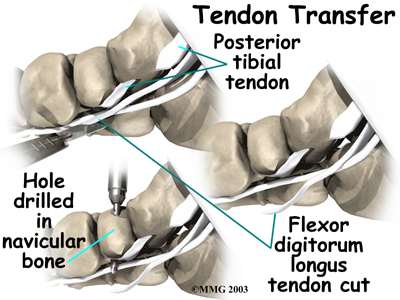

Tendon Graft

A badly degenerated or a ruptured tendon may require a tendon graft. Usually, another tendon in the foot, such as the tendon that flexes the four smaller toes (the flexor digitorum longus), is used as a tendon graft to work in place of the posterior tibial tendon.

Fusion